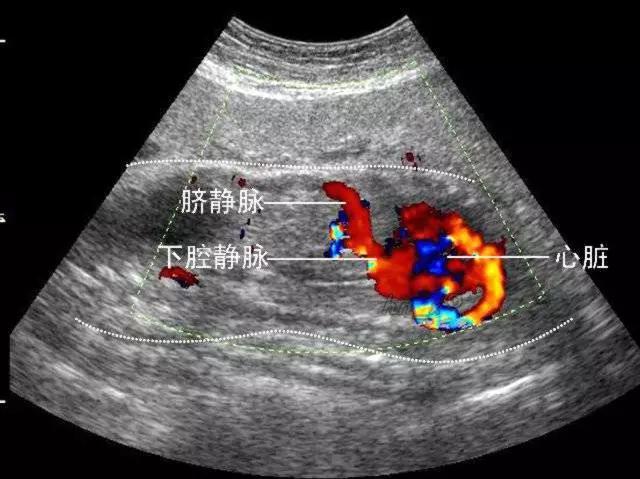

彩超具有彩色多普勒血流显像功能,可以显示病变区域的血管解剖结构、血流方向、血流速度和血流状态改变,可以明显提高对疾病的鉴别能力,提高诊断的准确性。

7. 心脏彩超

应用超声波扫描技术观察心血管结构、血流动力学状况及心功能的一种无创伤性检查方法,它可了解心脏各组成部分的形态以及功能状态,了解心脏内畸形位置、大小、大血管的关系以及其他畸形情况和病变程度。血管情况、病灶内血流血供情况-良恶性病变鉴别。

出现胸闷、胸痛、心悸等症状时,心电图是最简单易行的检查,但是心电图无法了解心脏内部的结构及功能。而心脏彩超可以观察心脏的运动情况,包括心肌的收缩、舒张,瓣膜的开放、关闭,血液流动的速度、方向,心脏与大血管的连接关系以及心脏及心包内的异常声像。因此,凡是有胸闷、胸痛、心悸症状的人群,建议做心脏彩超的检查。